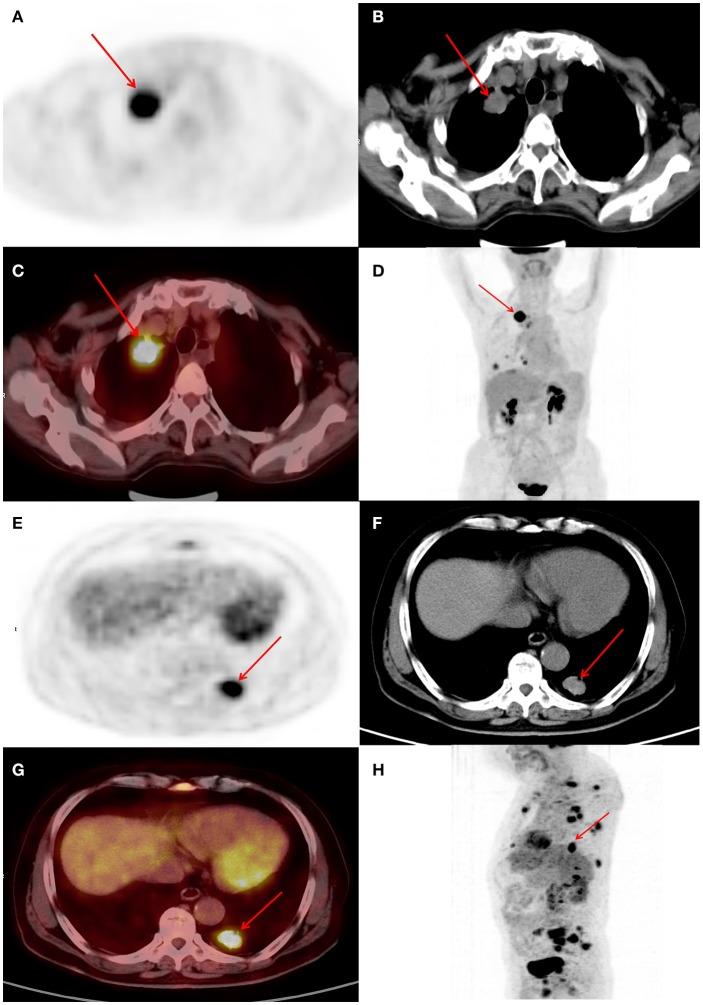

This study assessed the ability of metabolic parameters from Fluorodeoxyglucose positron emission tomography/computed tomography (F-FDG PET/CT) and clinicopathological data to predict epidermal growth factor receptor (EGFR) expression/mutation status in patients with lung adenocarcinoma and to develop a prognostic model based on differences in expression status, to enable individualized targeted molecular therapy. Metabolic parameters and clinicopathological data from 200 patients diagnosed with lung adenocarcinoma between July 2009 and November 2016, who underwent F-FDG PET/CT and mutation testing, were retrospectively evaluated. Multivariate logistic regression was applied to significant variables to establish a prediction model for mutation status. Overall survival for both mutant and wild-type was analyzed to establish a multifactor Cox regression model. Of the 200 patients, 115 (58%) exhibited mutations and 85 (42%) were wild-type. Among selected metabolic parameters, metabolic tumor volume (MTV) demonstrated a significant difference between wild-type and mutant mutation status, with an area under the receiver operating characteristic curve (AUC) of 0.60, which increased to 0.70 after clinical data (smoking status) were combined. Survival analysis of wild-type and mutant yielded mean survival times of 34.451 (95% CI 28.654-40.249) and 53.714 (95% CI 44.331-63.098) months, respectively. Multivariate Cox regression revealed that mutation type, tumor stage, and thyroid transcription factor-1 (TTF-1) expression status were the main factors influencing patient prognosis. The hazard ratio for mutant was 0.511 (95% CI 0.303-0.862) times that of wild-type, and the risk of death was lower for mutant than for wild-type. The risk of death was lower in TTF-1-positive than in TTF-1-negative patients. F-FDG PET/CT metabolic parameters combined with clinicopathological data demonstrated moderate diagnostic efficacy in predicting mutation status and were associated with prognosis in mutant and wild-type non-small-cell lung cancer (NSCLC), thus providing a reference for individualized targeted molecular therapy.

本研究评估了氟脱氧葡萄糖正电子发射断层扫描/计算机断层扫描(F-FDG PET/CT)的代谢参数及临床病理数据预测肺腺癌患者表皮生长因子受体(EGFR)表达/突变状态的能力,并基于表达状态差异建立预后模型,以实现个体化靶向分子治疗。对200例在2009年7月至2016年11月期间被诊断为肺腺癌且接受了F-FDG PET/CT检查及突变检测的患者的代谢参数和临床病理数据进行回顾性评估。对显著变量应用多因素逻辑回归来建立突变状态预测模型。分析突变型和野生型的总生存期以建立多因素Cox回归模型。在这200例患者中,115例(58%)表现出突变,85例(42%)为野生型。在选定的代谢参数中,代谢肿瘤体积(MTV)在野生型和突变型突变状态之间显示出显著差异,受试者操作特征曲线下面积(AUC)为0.60,在合并临床数据(吸烟状态)后增至0.70。野生型和突变型的生存分析得出平均生存时间分别为34.451(95%CI 28.654 - 40.249)个月和53.714(95%CI 44.331 - 63.098)个月。多因素Cox回归显示,突变类型、肿瘤分期和甲状腺转录因子-1(TTF-1)表达状态是影响患者预后的主要因素。突变型的风险比是野生型的0.511(95%CI 0.303 - 0.862)倍,突变型的死亡风险低于野生型。TTF-1阳性患者的死亡风险低于TTF-1阴性患者。F-FDG PET/CT代谢参数联合临床病理数据在预测突变状态方面显示出中等诊断效能,并且与突变型和野生型非小细胞肺癌(NSCLC)的预后相关,从而为个体化靶向分子治疗提供参考。